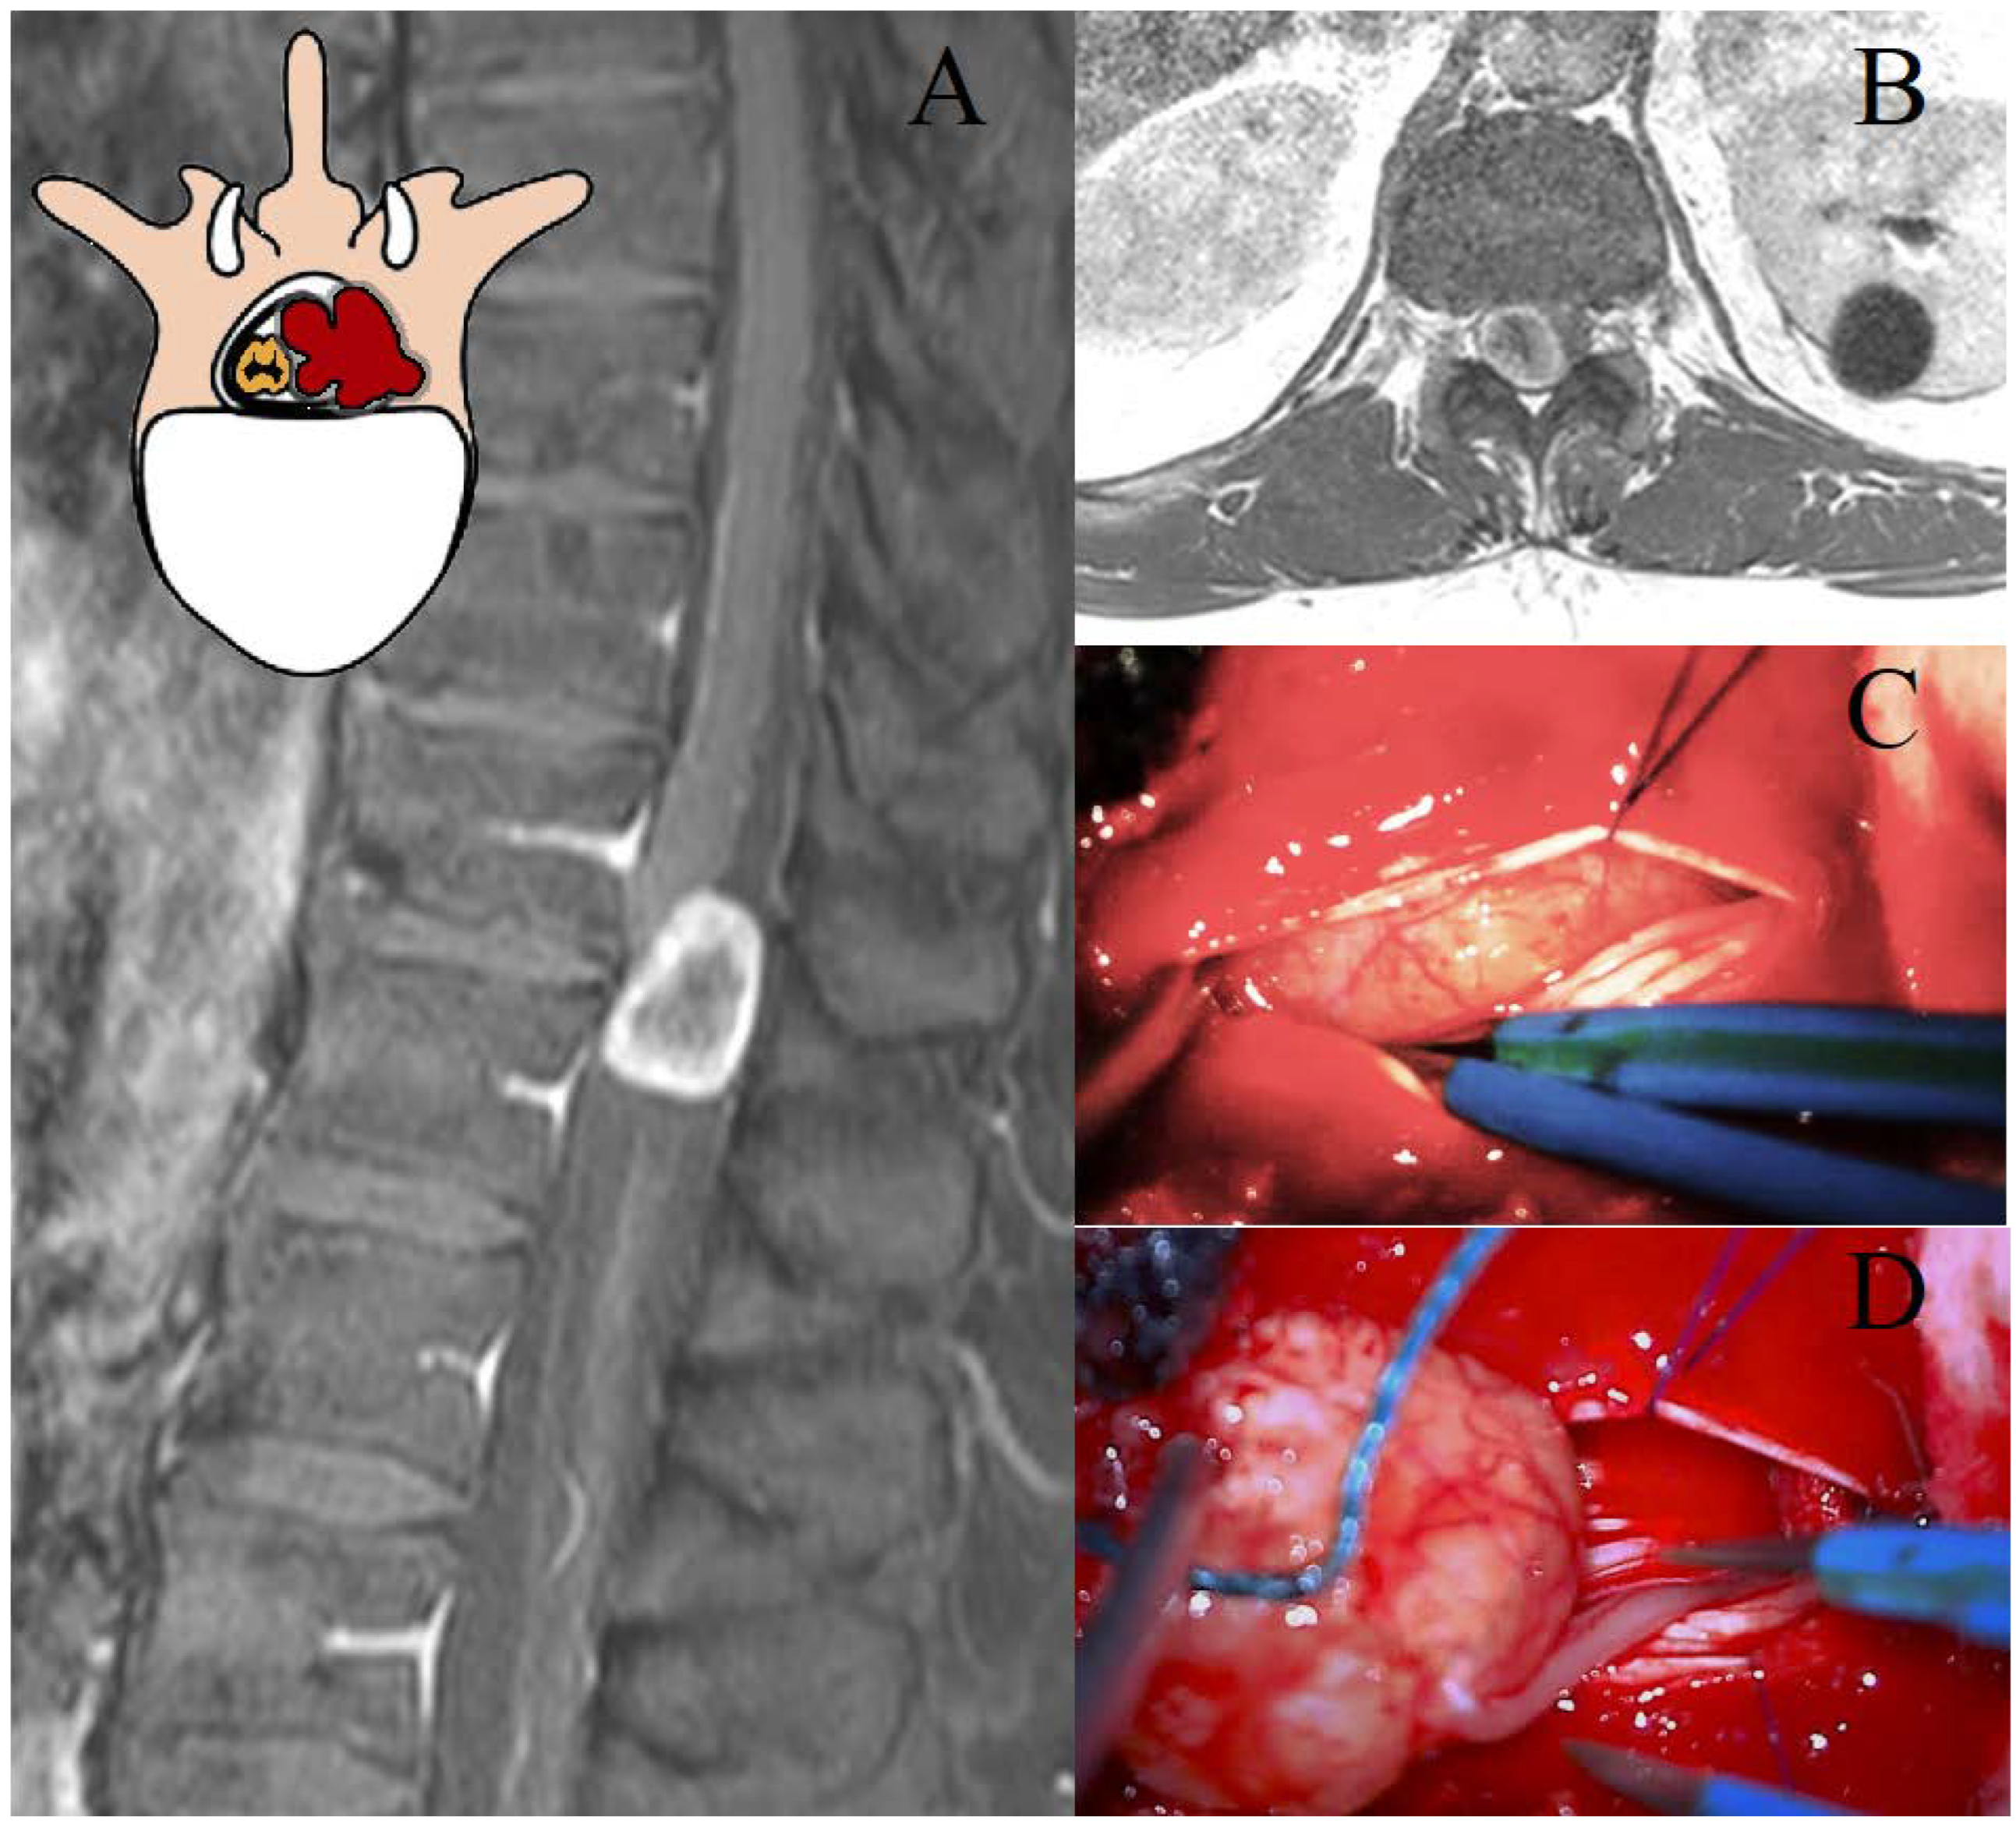

Eden class III lesions, or dumbbell tumors, represent a distinct surgical challenge due to their dual intraspinal and paravertebral extension [21]. Their management requires a tailored approach that ensures both adequate exposure and preservation of neurological structures, particularly in the presence of foraminal and mediastinal involvement [30]. Given these complexities, a combined neurosurgical and thoracic approach has been increasingly advocated to optimize tumor resection while minimizing morbidity [2,4,18]. In our study, two strategies were compared: exclusive neurosurgical resection (LCT/TPD) and a combined neurosurgical–thoracic approach with LCT + VATS [7]. The neurosurgical-only approach was associated with longer surgical times, lower GTR rates (62% vs. 100%, p < 0.01), and higher rates of dural complications, likely due to limited access to the extraforaminal component [8]. Conversely, the LCT + VATS approach enabled more effective tumor removal with comparable intraoperative blood loss and a significantly higher GTR rate, suggesting a clear advantage in complex cases requiring wider exposure. Despite these benefits, the postoperative length of stay did not differ significantly between the two groups, reflecting a similar overall surgical burden.

A simultaneous combined approach, as proposed in the recent literature, may further enhance surgical outcomes by ensuring superior control of both hemostasis and dural integrity [1,7]. The synchronous execution of the neurosurgical and thoracic phases allows for the direct management of epidural venous bleeding from both intraspinal and extraforaminal components, while also facilitating the timely repair of dural defects, thereby reducing the risk of cerebrospinal fluid leakage and its associated complications [7,10,15]. Although not representing a novel surgical technique per se, the synchronous single-stage combined neurosurgical and thoracoscopic approach (LCT + VATS) employed in our Eden III cohort reflects a recent and promising advancement in the management of complex dumbbell tumors. Its increasing adoption in high-volume centers, including ours, supports its inclusion as an emerging standard in appropriately selected cases. Additionally, this approach provides the optimal management of spinal stability, as the controlled and sequential resection minimizes excessive bony removal while allowing for the immediate intraoperative assessment of potential instability, reducing the need for secondary stabilization procedures (Figure 3).

Figure 3. Representation of a thoracic schwannoma, Eden Type III. (A) Preoperative sagittal T1-weighted MRI with contrast, showing a dumbbell-shaped lesion at the T7–T9 level, located in the left paramedian and intraforaminal region, with both intradural-extramedullary and significant paravertebral extension. (B) Axial MRI demonstrating the intraspinal, foraminal, and large paravertebral components of the lesion. (C) Intraoperative view following bone removal, exposing the intradural portion of the tumor. (D) Thoracoscopic-assisted dissection of the paravertebral component and the vascular pedicle of the lesion. (E) Resection of the foraminal component, with identification of the conjugation foramen. (F) Final surgical field during thoracoscopic tumor resection, showing the decompressed conjugation foramen (Black arrow).